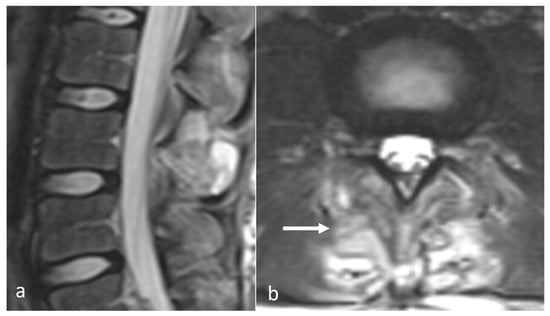

Characteristic imaging features include a close approximation of lumbar spinous processes (‘kissing spines”). CT may show reactive sclerosis, the resultant enlargement of the abutting spinous processes, and pseudoarthrosis formation. MRI can demonstrate interspinous bursal fluid as well as marrow oedema (Figure 1) [14]. Large bursal fluid collections can extend into the vertebral canal causing thecal sac compression.

Figure 1.

Sagittal STIR (short tau inversion recovery) image demonstrating Baastrup disease of lumber spinous processes (white arrow). Note the presence of reactive marrow oedema and sclerosis at the opposing surfaces of the spinous processes involved.